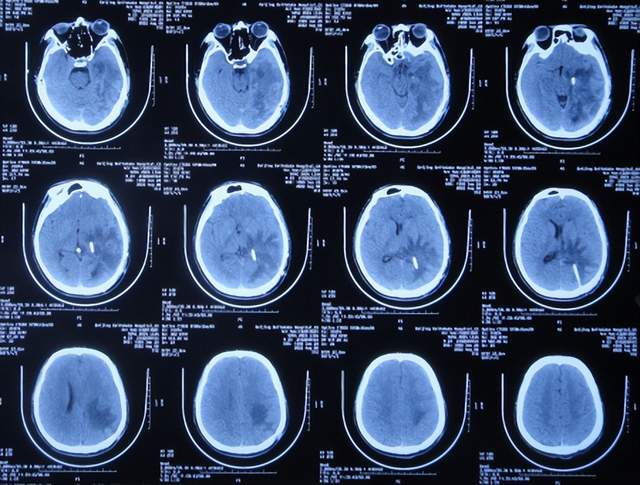

出院后5个月即2021年9月中旬,出现偶尔头痛的症状,因此于出院后7个月后即2021年11月10日,第2次来到李小勇脑脊液科;入院时:时有头痛(图-26),身体其他正常;查头颅CT示左侧颞角扩张(图-27)。

图-26:2021年11月10日入院时

图-27:入院时头颅CT

入院后2天即2021年11月12日,给予了颞角分流管调整术;术后第2天查头颅CT示颞角仍扩张(图-28)。

图-28:2021年11月14日头颅CT

入院治疗14天即2021年11月24日,查头颅CT示颞角缩小(图-29),患者头痛基本消失(图-30)。

图-29:2021年11月24日头颅CT

图-30:2021年11月24日

2022年1月4日(李小勇脑脊液科第2次治疗55天)出院。出院时:头痛已消失1月余(图-31),身体一切正常,查头颅CT示未见异常(图-32)。

图-31:2022年1月4日出院时

图-32:出院时头颅CT